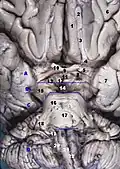

Frontální řez pontem. -

Lidský mozek – frontální řez.